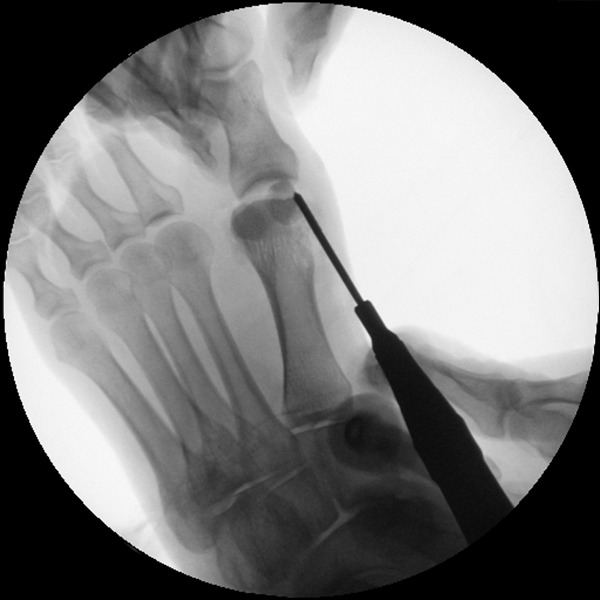

• Positionierung des Bildwandlers: 90° Winkel zum Os metatarsale I. Benötigt wird die Durchleuchtung des Vorfußes a.p., seitlich und schräg.

Operationstechnik

Der von Isham/Reverdin beschriebenen minimal invasiven Technik zur Korrektur einer Hallux valgus Deformität liegen 4 Operationsschritte zu Grunde:

1. Abtragung der Exostose am Köpfchen des 1. Mittelfußknochens

2. Subcapitale intraartikuläre Osteotomie

3. Laterales Release

4. Akin Osteotomie der Großzehengrundphalanx

Die Folge der Operationsschritte sollte strikt von 1. - 4. erfolgen, da ansonsten die mediale Closing Wedge Osteotomie bei vorzeitigem lateralem Release und/oder Akin Osteotomie nicht geschlossen werden kann. Nach der von Isham beschriebenen Originaltechnik finden Implantate keine Anwendung, zur Sicherung und besseren Fixation können osteosynthetische Verfahren angewandt werden (siehe auch Fehler, Gefahren und Komplikationen).